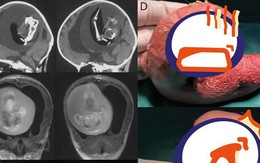

Mang thai đôi nhưng chỉ sinh một bé, 1 năm sau bố mẹ đưa con gái đi khám mới phát hiện sự thật đáng sợ nằm trong não

12/03/2023 12:10

Kết quả chụp CT não đã khiến gia đình lẫn các bác sĩ bất ngờ vì là trường hợp siêu hiếm trên thế giới.